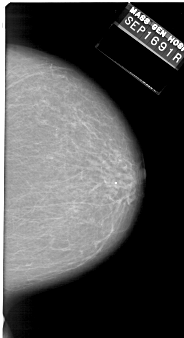

A_1140_1.LEFT_MLO

DATE_OF_STUDY 16 9 1991

PATIENT_AGE 81

DENSITY 2

LEFT_MLO LINES 6526 PIXELS_PER_LINE 3301 BITS_PER_PIXEL 12 RESOLUTION 43.5 OVERLAY

FILE: A_1140_1.LEFT_MLO.OVERLAY

TOTAL_ABNORMALITIES 1

ABNORMALITY 1

LESION_TYPE MASS SHAPE ARCHITECTURAL_DISTORTION MARGINS SPICULATED

ASSESSMENT 5

SUBTLETY 4

PATHOLOGY MALIGNANT

TOTAL_OUTLINES 2